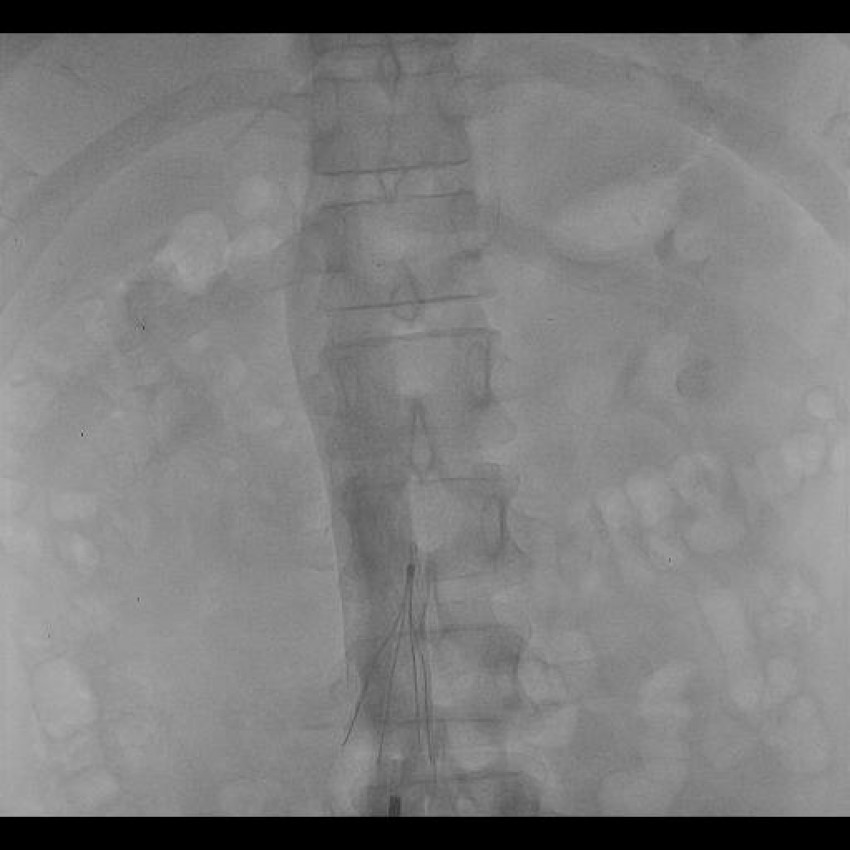

Doctors often use inferior vena cava filters to remove a fistula from the body, commonly known as IVC filters. Venous thromboembolism (VTE) is a common symptom that can be seen in the human body when the fistula doesn't adequately perform functions. Most medical professionals prefer anticoagulation as the treatment of VTE. IVC filters get used to performing anticoagulation only in selected patients.

There are primarily two types of inferior vena cava filters: Permanent IVC filters and Temporary IVC filters. In the case of permanent IVC filters, the patient will get long-term relief. This type of IVC filter is because the filter will cause absolute contraindications for anticoagulation. Let's consider temporary IVC filters. Pulmonary Embolism (PE) risk will get reduced, which is much greater, as seen in the case of permanent IVC filters.

There are some classical signs which indicate that you require IVC filter placement.

- Anticoagulation failure.

- Rise of complication during anticoagulation which leads to the cessation of dialysis.

- Contradiction during anticoagulation.

- Progression of DVT at the time of therapeutic anticoagulation.